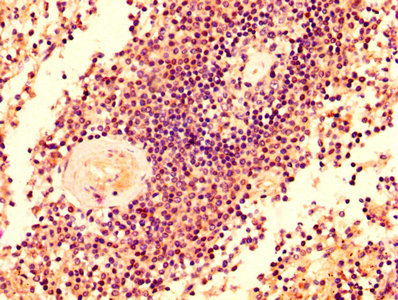

IHC image of CSB-PA00969A0Rb diluted at 1:500 and staining in paraffin-embedded human tonsil tissue performed on a Leica BondTM system. After dewaxing and hydration, antigen retrieval was mediated by high pressure in a citrate buffer (pH 6.0). Section was blocked with 10% normal goat serum 30min at RT. Then primary antibody (1% BSA) was incubated at 4°C overnight. The primary is detected by a biotinylated secondary antibody and visualized using an HRP conjugated SP system.